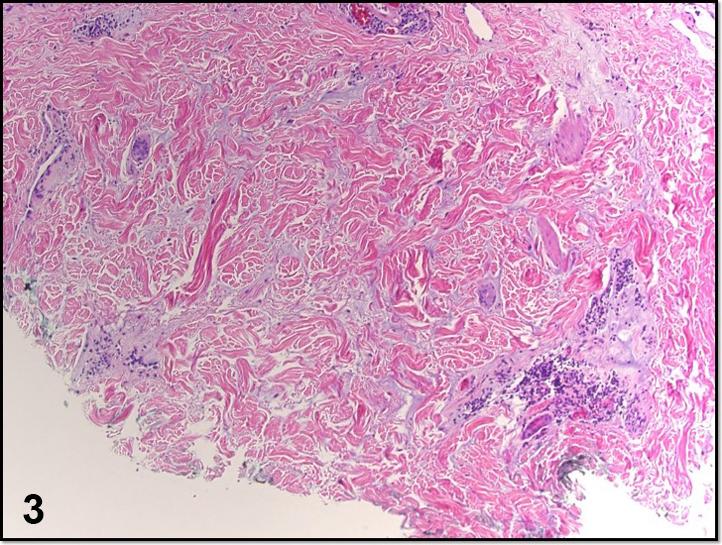

Curvilinear violaceous plaques along Blaschko lines.

Curvilinear violaceous plaques along Blaschko lines.沿布拉斯科线分布的曲线状紫罗兰色斑块。